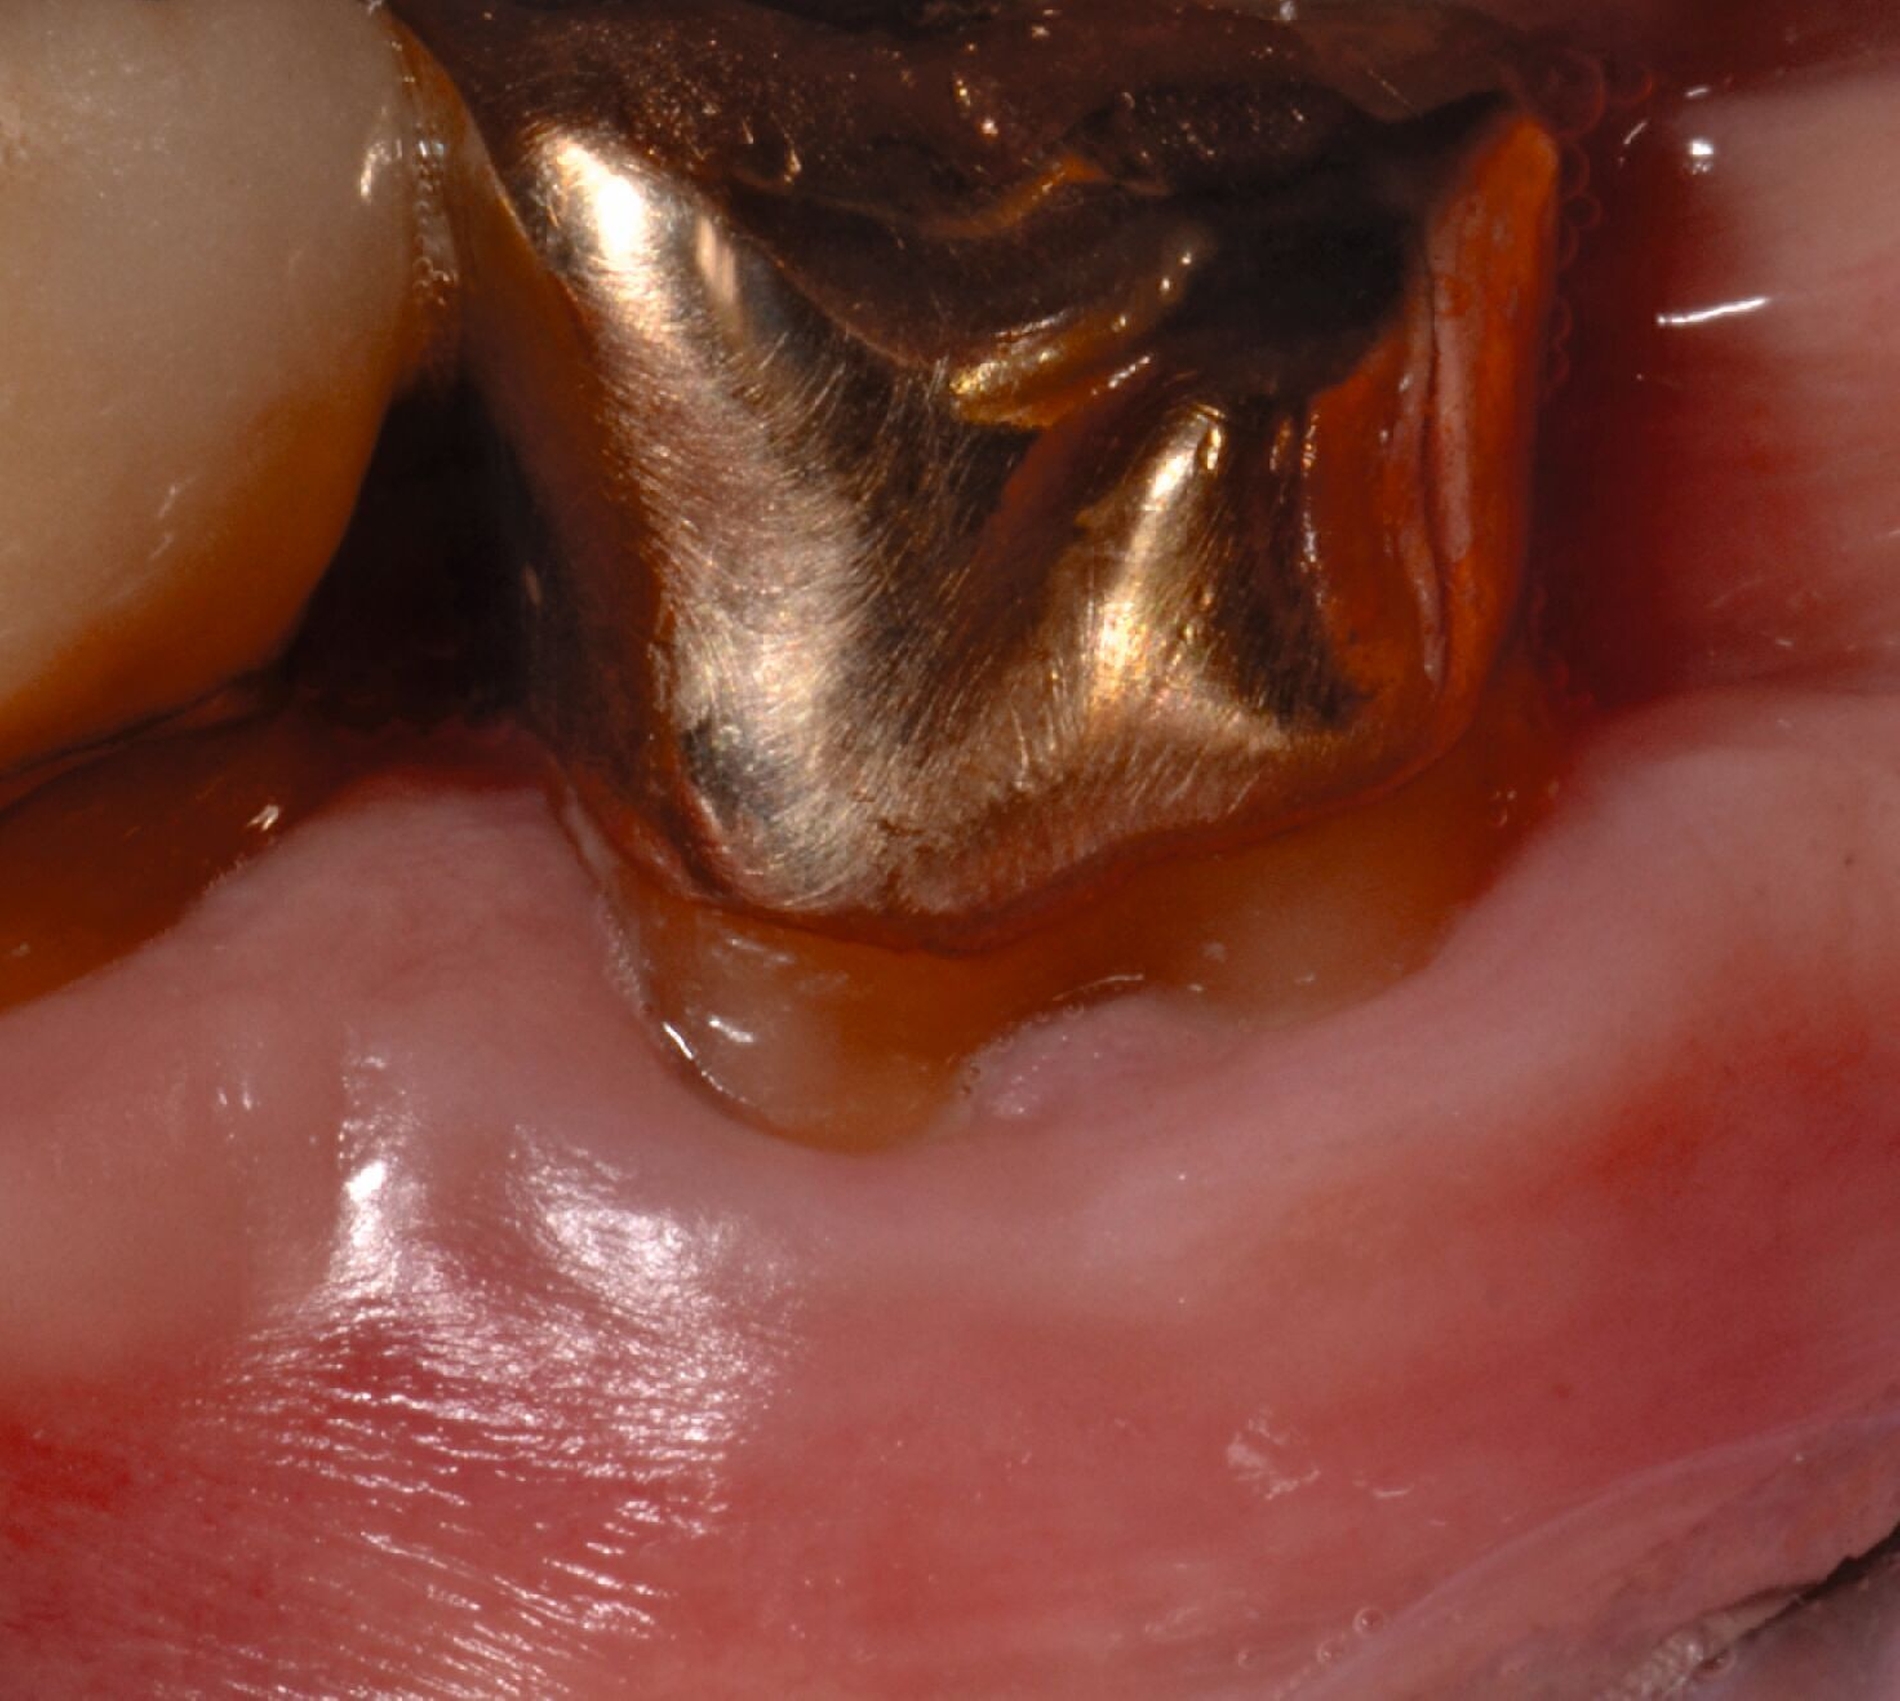

Ziel ist es, einen ausreichenden Zugang zum Defekt für eine sorgfältige Instrumentierung und die Applikation des Biomaterials zu erhalten. Bei isolierten Defekten können vertikale Entlastungsinzisionen verwendet werden. Alternativ kann der Lappen nach lateral zu den benachbarten Zähnen erweitert werden. Keratinisiertes Gewebe sollte durch intrasulkuläre Inzision und die Anhebung eines Mukoperiostlappens erhalten werden. Das Granulationsgewebe wird entfernt und die freiliegenden Wurzeloberflächen werden sorgfältig mit Handinstrumenten, oszillierenden Scalern (optional mit fein diamantierten Spitzen) oder rotierenden Instrumenten gereinigt. Wurzelanomalien wie Schmelzvorsprünge/-perlen sollten entfernt werden. Wenn EMD Teil der Regenerationsstrategie ist, wird es in der Regel nach einer zweiminütigen Wurzelkonditionierung mit Ethylendiamintetraacetat (EDTA) und Spülung mit steriler Kochsalzlösung angewendet. Anschließend kann ein Knochentransplantat/-ersatzmaterial verwendet werden, um den Furkationsdefekt aufzufüllen.

Alternativ kann eine GTR-Barrieremembran mit oder ohne zusätzlichen Defektfüller appliziert werden. Die Barrieremembran wird mit einer resorbierbaren Umschlingungsnaht befestigt, um den Furkationseingang abzudecken und die Wund- und Koagulumstabilisierung zu fördern. Um eine vollständige Abdeckung der Barriere zu ermöglichen, kann das Periost durchtrennt werden, um den Lappen leicht koronal zu verschieben. Der Lappen wird mit einer Umschlingungsnaht und Einzelknopfnähten über den vertikalen Entlastungsinzisionen oder mit interdentalen Nähten im Fall eines lateral extendierten Lappens in einer koronalen Position gesichert. Der Patient wird angewiesen, für einen Zeitraum von bis zu vier Wochen auf die mechanische Plaqueentfernung im Operationsgebiet zu verzichten. Während dieser Zeit werden Chlorhexidin-Spülungen oder -Gel verwendet. Der Patient kehrt zur Kontrolle der Wundheilung nach ein und zwei Wochen zurück, wenn die Nähte entfernt werden. Die Interdentalhygiene und die mechanische Plaqueentfernung werden nach vier Wochen wieder aufgenommen. Zudem wird ein individuelles Recallprogramm zur unterstützenden Parodontitistherapie (UPT) festgelegt.